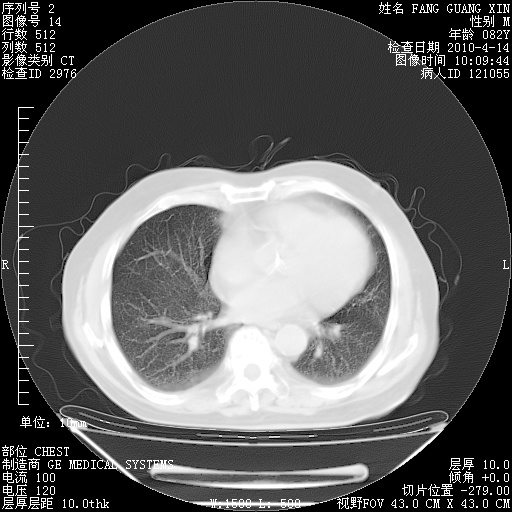

4月14日肺部CT

23.JPG

24.JPG

25.JPG

26.JPG

肺部CT平扫未见异常。